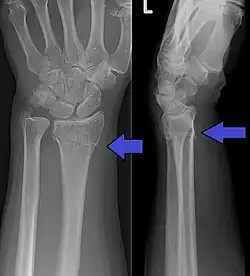

Distale Radiustrümmerfraktur mit Ulnabeteiligung und ihre Behandlung: Unfallbild von oben -

…und von der Seite her geröntgt -